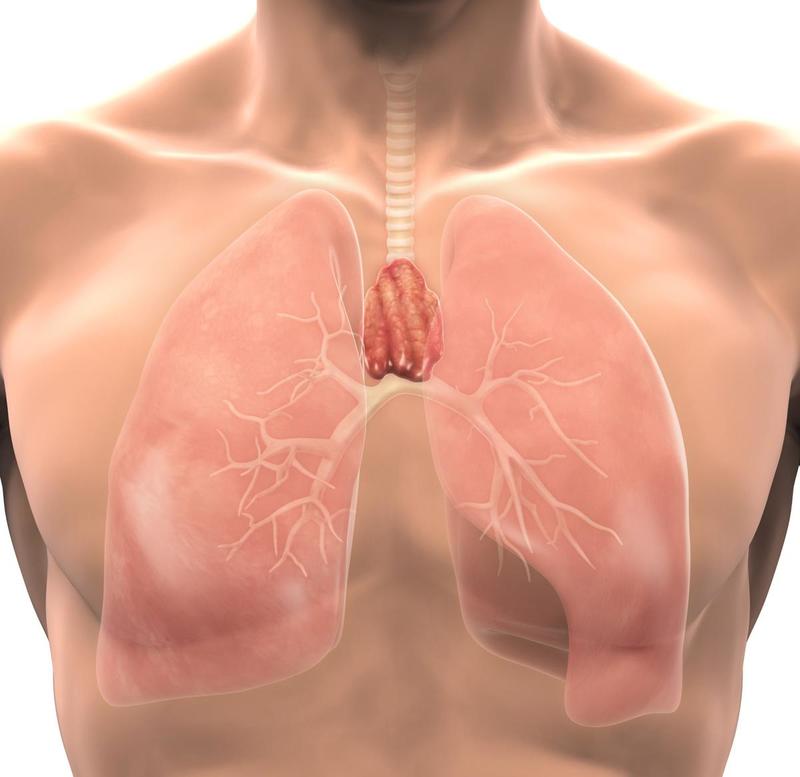

Тимомегалия: что это такое и как проявляется